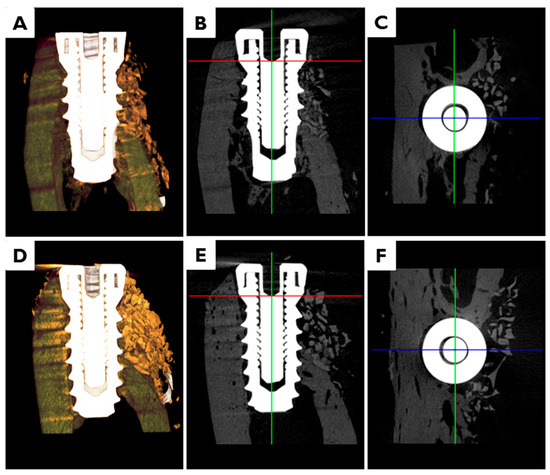

In animals transplanted with CM or EI-BCM, bone graft materials were observed in peri-implant dehiscence defect areas at eight weeks after surgery (Figure 7). Volumetric measurements are summarized in Table 1. Volumes of new bone (NBV, mm3), remaining bone substitute volumes (RBV, mm3), totally augmented volumes (TAV, mm3) and non-mineralized tissue volumes (NMV, mm3) were not significantly different in CM and EI-BCM transplanted animals at eight weeks (p > 0.05).

Figure 7.

Micro-computed tomography (μCT) images. In animals transplanted with: CM (A–C); or EI-BCM (D–F), bone graft materials were observed in peri-implant dehiscence defect areas at eight weeks after surgery. (A,D) 3D images; (B,E) 3D reconstructed images of mesiodistal sections; and (C,F) 3D reconstructed images of occlusal sections.